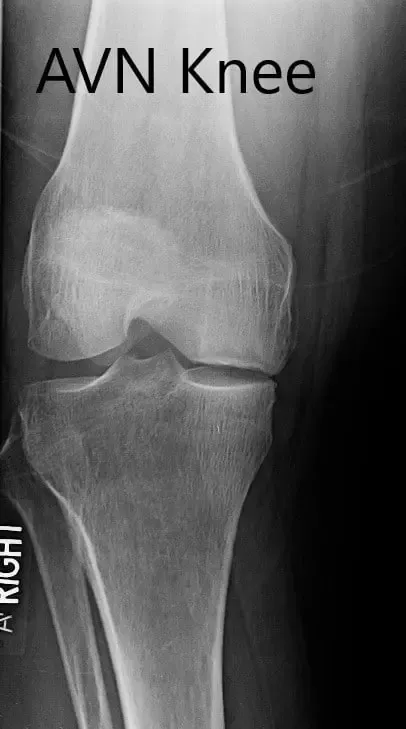

Los estudios de imagen revelaron osteoartritis severa en el compartimento medial de la rodilla derecha junto con artritis patelofemoral. La resonancia magnética reveló la progresión de una fractura subcondral previa en el cóndilo femoral medial, lo que ahora resulta en una región de necrosis avascular y una línea de fractura subcondral prominente llena de líquido que puede medir hasta 2,8 cm. Hubo un colapso leve del margen articular y un edema severo de médula ósea circundante.

Radiografía preoperatoria de la rodilla derecha en vistas anteroposterior y lateral.